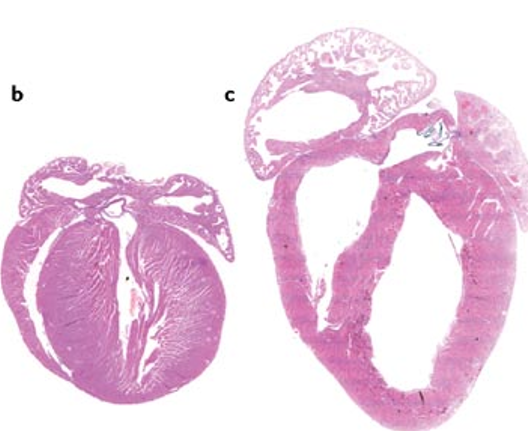

Which is concentric/eccentric ventricular hypertrophy?

Concentric - left (thicker walls)

Eccentric - right (dilated chamber lumen and normal walls)